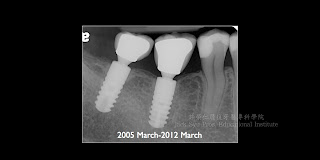

Ankylos植牙系統文獻回顧與臨床病例報告之三